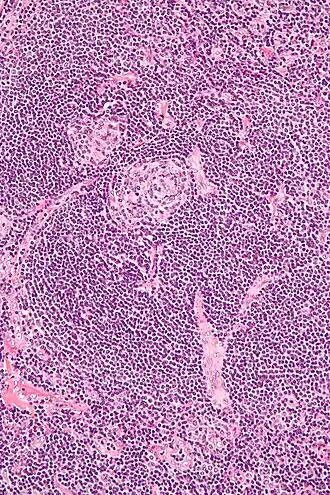

Vue au microscope montrant l'expansion caractéristique de la zone du manteau du ganglion.

Bien que non considérée comme un cancer, cette prolifération de lymphocytes est assez similaire à un lymphome, et d'autres recherches sont nécessaires pour caractériser les petites populations de cellules néoplasiques[8].